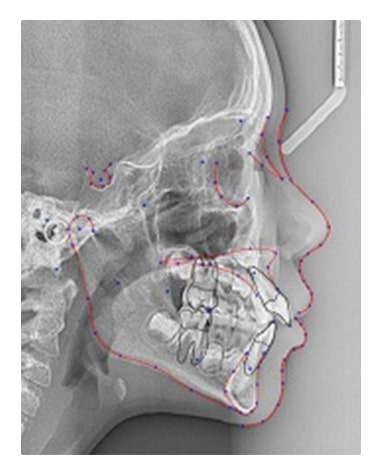

歯や顎の骨を3次元で撮影できる「歯科用CT」と、頭部全体を撮影できる矯正歯科専用の「セファログラム」の複合機です。2種類のレントゲンを活用し、適切な診査・診断を行っています。